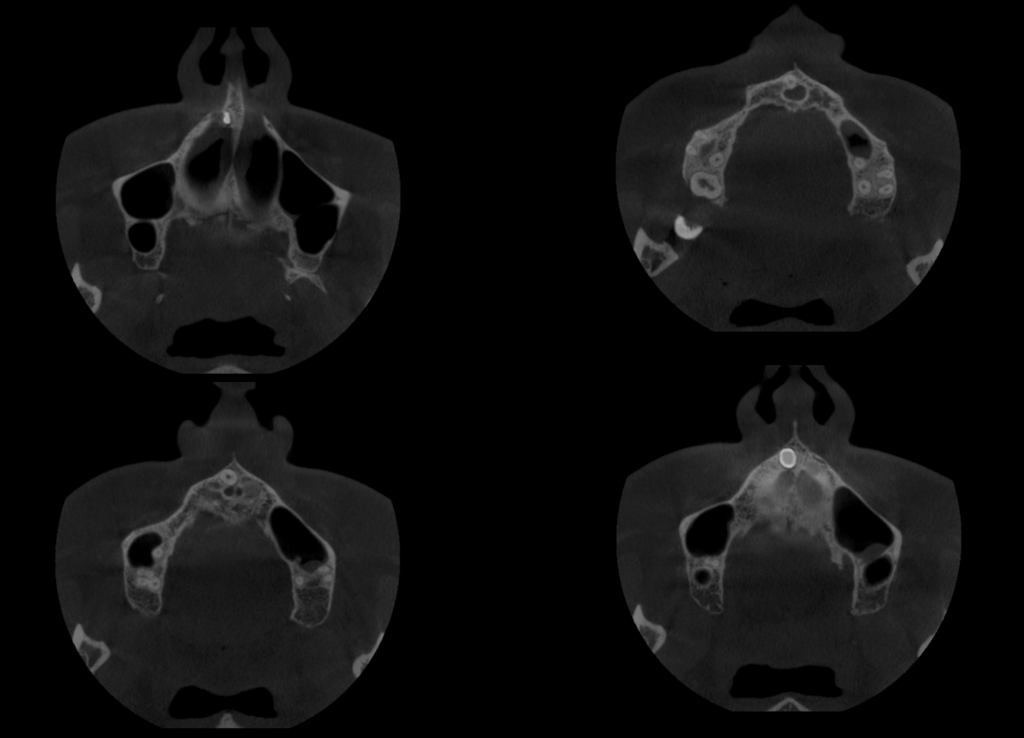

A la evaluación de la tomografía volumétrica (CBCT) en los cortes axiales (Figura 2) y transaxiales (Figura 3), se aprecia pieza supernumeraria en posición invertida localizada a nivel de pieza 11, segmento radicular en contacto con la cortical de conducto nasopalatino, segmento coronario en contacto con el piso de fosa nasal derecha.

CORTES AXIALES